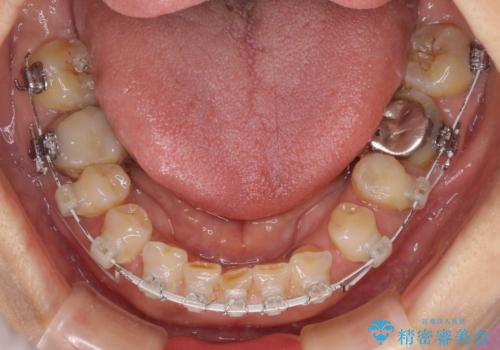

上顎はほぼ全ての歯をセラミッククラウンにて補綴治療を行う必要があるため、気になるデコボコや深い咬み合わせを改善するために下顎と上顎の臼歯部の矯正治療を行うこととしました。

並行して左下にはインプラントを埋入し、矯正治療を終えると同時に補綴治療を行うこととしました。

過蓋咬合(下顎前歯が隠れてしまうほどの深い咬み合わせ)のため、スムーズに歯が動かず矯正治療に時間がかかりましたが、無事に仕上げることができました。